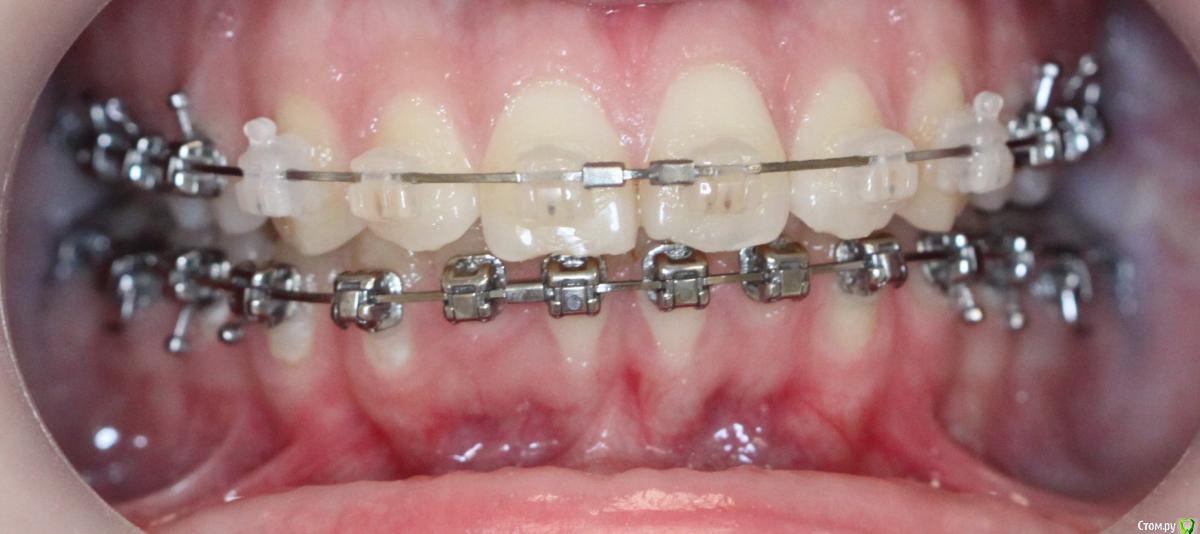

annurka Опубликовано 12 сентября, 2017 Поделиться Опубликовано 12 сентября, 2017 (изменено) здравствуйте! 24 года, дисфункция ВНЧС, дистальный прикус (1,4см), ортодонтическое лечение начато с ношения каппы для разгрузки сустава (привыкла подтягивать НЧ к верхней) в 2012 году. проведено лечение: удаление всех 8к (непрорезавшиеся), расширение ВЧ (аппарат дерихсвайлера), выравнивание зубных рядов, сепарация нижних резцов (резцы были наклонены), места не хватило - удаление 2 нижних 4к, выравнивание кривой шпее, двухчелюстная остеотомия; выравнивание окклюзионных контактов (резиновые тяги) проблема: между верхними и нижними резцами расстояние 5мм к трг (внизу фото) есть расшифровка.все идет к снятию брекетов, и с эстетической точки зрения меня все устраивает. но не до конца устраивает в функциональном плане (я не могу пропихнуть палец между зубными рядами, как раньше, но все также подтягиваю челюсть кпереди когда ем, говорю)стараюсь контролировать это, но даже улыбнуться не могу не подтянув - иначе у меня некрасиво вырисовывается подбородок, неправильно произношу звуки при разговоре.сразу после остеотомии состыковка резцов была ок - нижние зубы были за верхними, но мы с ортодонтом занялись состыковкой и других зубов (которые тогда не соприкасались), и когда добились контактов жующих сторон, разошлись резцы.UPD: и еще есть черные треугольники на НЧ - с ними тоже очень хочется разобраться лечащий ортодонт говорит, что это в целом норма, с учетом моего случая. и возможно это так, но я очень хочу послушать еще мнений, возможно стоит удалить 2 зуба наверху, чтобы верхняя челюсть подошла по размер нижней? [боюсь что простой сепарации может не хватить и как в случае с нижними резцами придется и сепарацию делать, и удалять зубы.] может быть еще есть другой способ добиться нормального прикуса, без "нюансов"?изначально я пошла на все это лечение, чтобы остановить разрушение сустава (однажды проснулась и не смогла рот даже открыть, еще до лечения), полагала, что брекеты и члх исправят если не ситуацию, то причину, но я все еще двигаю НЧ вперед к ВЧ. с остеотомии прошел почти год (поэтому на изменение картины эластиками я уже не надеюсь), брекеты ношу почти 4 года. заранее всем спасибо за отклик! Изменено 12 сентября, 2017 пользователем annurka 1 Ссылка на комментарий

annurka Опубликовано 13 сентября, 2017 Автор Поделиться Опубликовано 13 сентября, 2017 (изменено) А До лечения есть ТРГ посмотреть? И фото какие-нибудь?есть трг сверху - сразу после остеотомии, снизу - через полгода после (когда резцы отошли друг от друга на 5мм) до лечения вообще точно делал ортодонт (снимки, слепки, фото), если в клинике это сохранили, я смогу сфотографировать. далее фото в процессе лечения - 4ки нижние еще не удалены, один хирург был готов так оперировать, другой сказал, что наклон нижних резцов неправильный и нужно как и было запланировано удалить 4ки, сепарации недостаточно.челюсть расслаблена как есть: НЧ подвинута к ВЧ для наглядности: есть фото слепков того периода, но форум ругается на слишком большой размер. если нужно - уменьшу залью) Изменено 13 сентября, 2017 пользователем annurka 1 Ссылка на комментарий

annurka Опубликовано 23 сентября, 2017 Автор Поделиться Опубликовано 23 сентября, 2017 (изменено) решила не трогать свои 4ки) подскажите кто-нибудь живой, сепарации верхних зубов будет достаточно?и если сепарировать, то только резцы (от клыка до клыка) или лучше весь ряд, или наоборот только боковой отдел? Изменено 23 сентября, 2017 пользователем annurka Ссылка на комментарий